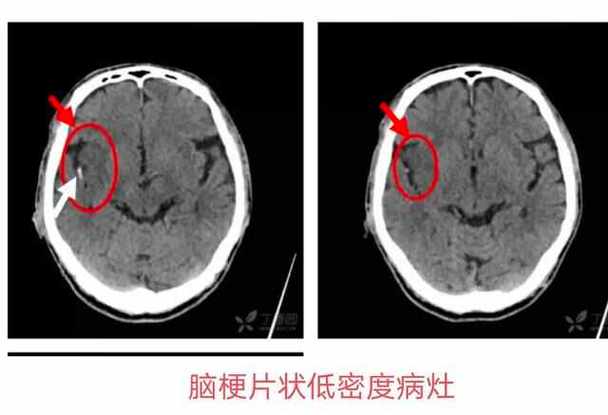

脑内少许腔梗 (Lacunar Infarction)

- 什么是“腔梗”? “腔梗”是“腔隙性脑梗死”的简称,它是一种特殊的脑梗死,不是我们通常想象的那种大面积的、致命的“中风”,它是因为大脑深部的一些非常细小的穿通动脉发生堵塞,导致其供应的脑组织缺血、坏死,形成一个很小的“洞”或“腔隙”。